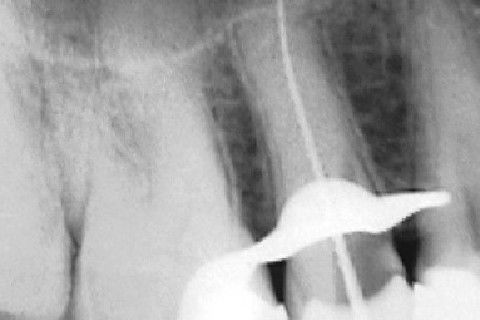

Calcificação Distrófica